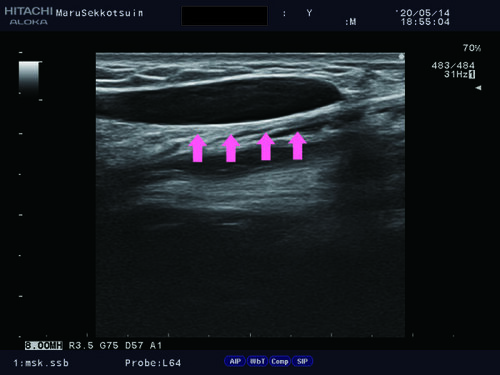

いつものようにしっかり問診、視診、触診後、確認の為、エコー検査。

上腕二頭筋長頭腱2.jpg上腕二頭筋長頭腱3.jpg

上の写真を診て頂いてお察しの方もいらっしゃると思いますが、

結果は「上腕二頭筋長頭筋腱移行部断裂」でございました。